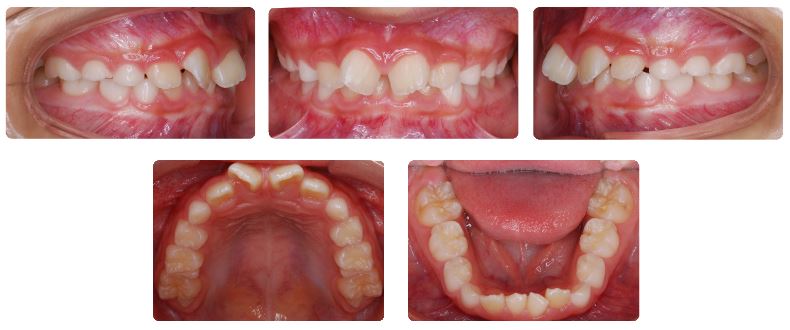

診断名:前歯部叢生を伴う過蓋咬合

前歯の噛み合わせが深く、下あごの前歯が上あごの前歯に隠れて見えない状態です。

最初の半年間は、上あごに取り外しのできる歯列側方拡大装置を夜間のみ使用していただきました。

前歯の歯並びに少し隙間ができたタイミングで、マウスピース型の機能的矯正装置であるトレーナーを混合歯列期の間、現在まで使用しています。